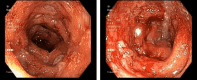

Figure 1

Figure 1. Rectum: erythematous, edematous and friable mucosa with loss of vascularity, and superficial ulcerations with exudate

Figure 2

Figure 2. Sigmoid colon: erythematous, edematous and friable mucosa with loss of vascularity, and superficial ulcerations with exudate, as well as multiple small-mouthed diverticula